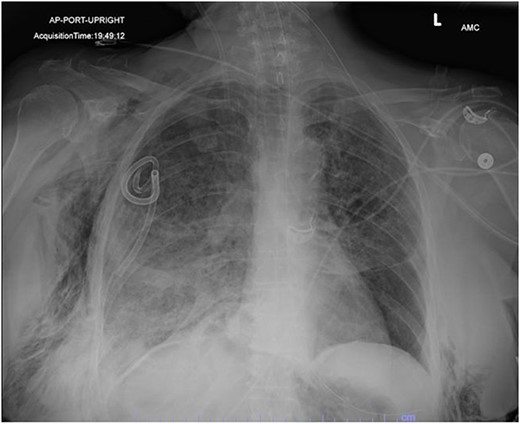

On Hospital Day 2, an interval CXR showed continued resolution of the right-sided pneumothorax but worsening subcutaneous emphysema of the bilateral chest wall and pneumoperitoneum (Fig. 3). Surgical consultation was sought, leading to diagnostic laparoscopy. In the abdomen, emphysematous changes within the gastrohepatic ligament and omental adhesions to the anterior abdominal wall were visualized (Figs 5 and 6). Laparoscopic exploration revealed no diaphragmatic injury or perforated viscera but identified emphysematous changes throughout the preperitoneal space, small and large bowel mesentery, and right paracolic gutter (Figs 7 and 8). Immediate post-op CXR no longer showed evidence of pneumoperitoneum (Fig. 4). The patient was transferred back to the ICU and extubated after three days on Day 5. After the removal of chest tube and transfer to a medical floor on Day 8, the patient developed aspiration pneumonia that was treated with antibiotics. She was discharged on Day 15.

AP upright chest radiograph showing intraabdominal free air, right-sided chest tube in place, and bilateral chest wall subcutaneous emphysema that is worse on the right. Bilateral patchy airspace disease is noted as well.